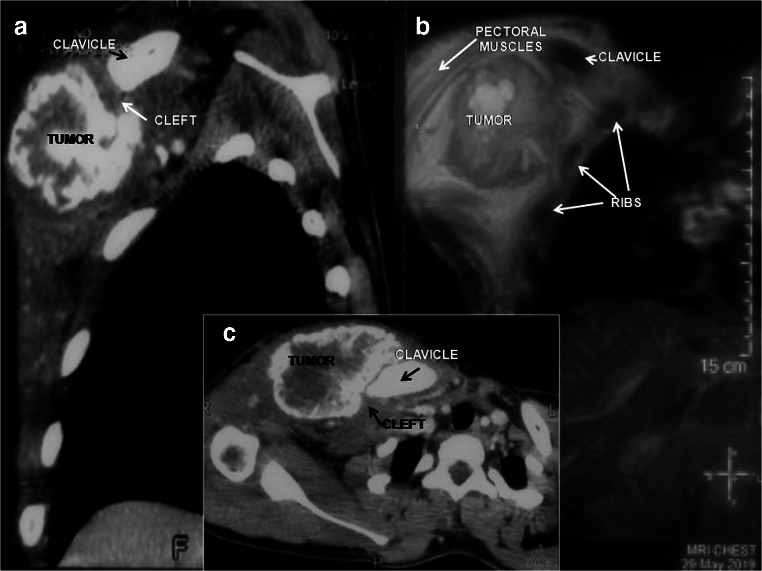

Chest x-ray showed increased density over the right hemithorax with no lytic lesions or fractures in the underlying bones (Fig. 1b). Computerized tomogram (CT) and magnetic resonance imaging were suggestive of a MO, characterized by a well-defined, irregular, heterogeneously enhancing, peripherally calcified mass. It was arising from the chest wall from under the medial third of the clavicle and was growing into the overlying pectoralis major muscle. There were no features of malignancy (Fig. 2a–c). The diagnosis was confirmed by a needle biopsy and the tumor was excised completely. The patient had an uneventful recovery and is doing well 8 months after surgery.

Fig. 2.

Reconstructed sagittal CT image (a), magnetic resonance image (b), and axial CT image (c) of the chest, showing the irregular peripherally calcified mass, closely related to the medial end of the right clavicle, but separated by a cleft of lucency

In the early stages (< 4 weeks), CT shows a lesion iso- to hypo-dense to muscle without calcification. In the intermediate period (4–8 weeks), amorphous patchy calcifications appear, which later becomes a dense peripheral shell of calcification. With further maturation (> 8 weeks), the lesion becomes smaller and may exhibit more diffuse calcification and ossification [5, 6]. It is typically separated from the adjacent bone by lucency or a cleft with no evidence of local invasion [1, 2]. Histologically, pluripotent cells and periosteal osteoblasts in the injured tissue are thought to initiate this abnormal repair process centripetally, resulting in a MO [1, 5]. Thus, in a mature lesion, three zones are seen, a central undifferentiated zone, surrounded by areas of osteoid and mature bone formation with calcification (Figs. 3a–c and 4a, b). This phenomenon named zonation is not seen in malignancies [1, 5]. Thus, a needle biopsy from the central area may show atypical cells suspicious of malignancy [5].